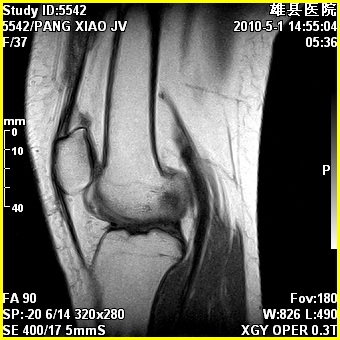

标题: MRI2894:患者右膝关节疼痛两月余,无明显外伤史 [打印本页]

标题: MRI2894:患者右膝关节疼痛两月余,无明显外伤史

右股骨下端前内侧类圆形异常信号,位于干骺端,呈长t1长t2改变,但信号不均,t1图上病灶中心见小片状稍高信号影,t2图上见散在稍低信号影,stir像呈高信号,因病灶较小,缺乏特征性改变,结合患者年龄及部位,考虑嗜酸性肉芽肿可能性大。胫骨关节面下的小囊状异常信号,如果一元论考虑则为嗜酸性肉芽肿,不过发生在这个部位的少见,二元论考虑为邻关节骨囊肿。半月板与前后交叉韧带均未见异常。

右股骨下端前内侧干骺端囊性良性病变,考虑 1内生软骨瘤 2骨囊肿 3肉芽肿。